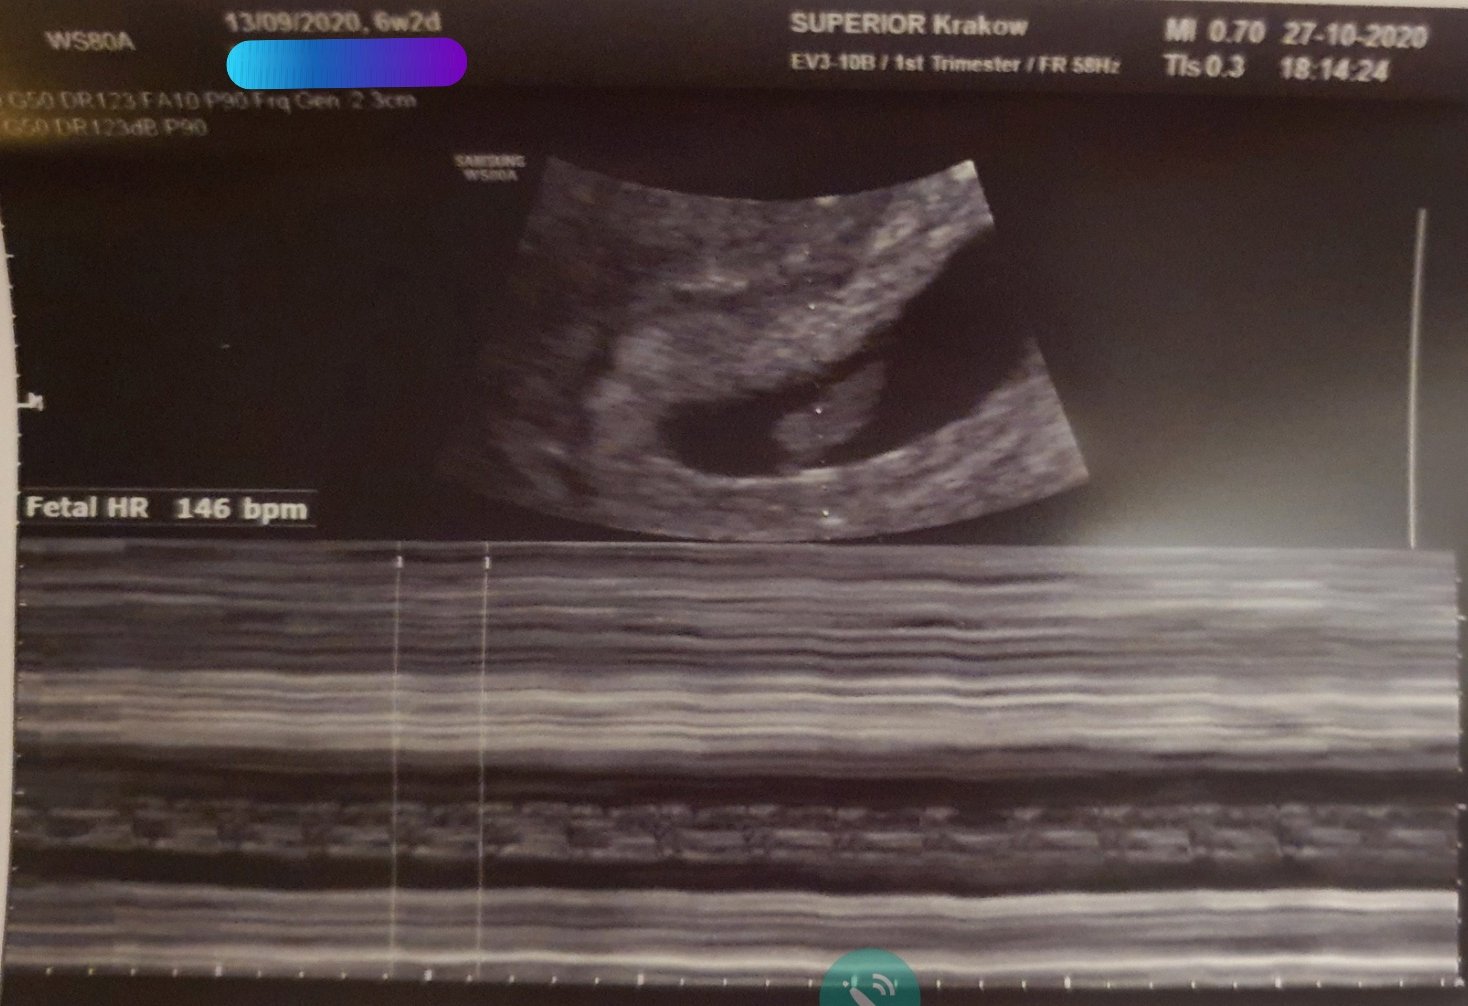

Dziewczyny ja już po mojej wizycie :) wszystko ok. Serducho bije. Tetno 146 :) kawał dzieciątka już jest. W opisie 9.8mm a ze zdjęcia 9.4mm wiec nie wiem czy lekarz sie walnął czy złapał jeszcze jakiś większy pomiar w miedzyczasie. Wg OM wychodzi 6+2, a wg USG 6+6. Pewnie to dlatego że mam krótkie cykle 24-25 dni. Lekarz powiedział że to już poważna ciąża. Przewidywany porod 16 czerwca 2021 plus/minus 4 dni. Wizyta mimo że prywatna i kosztowała "tylko" 280zł też z godzinną obsuwą, a że dotarłam do lekarza godzinę przed czasem to koczowałam na miejscu 2h :/ dopiero zaczełam obiad jeść przed chwilą.

Dziewczyny ja już po mojej wizycie :) wszystko ok. Serducho bije. Tetno 146 :) kawał cieciątka już jest. W opisie 9.8mm a ze zdjęcia 9.4mm wiec nie wiem czy lekarz sie walnął czy złapał jeszcze jakiś większy pomiar w miedzyczasie. Wg OM wychodzi 6+2, a wg USG 6+6. Pewnie to dlatego że mam krótkie cykle 24-25 dni. Lekarz powiedział że to już poważna ciąża. Wizyta mimo że prywatna i kosztowała "tylko" 280zł też z godzinną obsuwą, a że dotarłam do lekarza godzinę przed czasem to koczowałam na miejscu 2h :/ dopiero zaczełam obiad jeść przed chwilą.